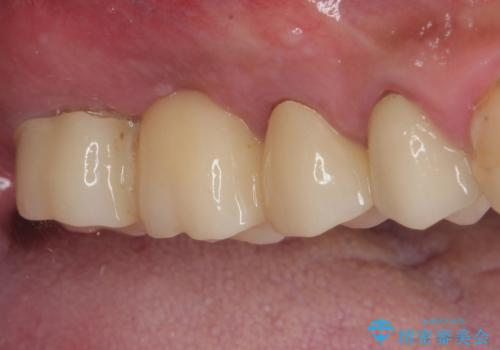

術後にインプラントの安定値を測定し、十分な値が達成された後、速やかにセラミッククラウンにて補綴治療を行うこととしました。